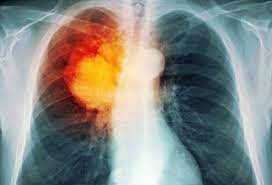

What Are Symptoms Of Lung Cancer In Humans : Lung Cancer Causes Symptoms Treatments Omega Hospital Health File Telugu News Tv5 News Youtube - Some of the most common are horner's syndrome, superior vena cava syndrome, and paraneoplastic syndrome.. Cough that produces thick mucus coughing helps to rid your body of the mucus produced from inflammation of the airways. Lung cancer signs and symptoms are not apparent in the early stages of the disease according to the national institutes of health (nih), so be aware of the following:. Cough, which can sometimes be bloody. Symptoms practically do not differ from clinical symptoms of lung cancer. Like many other types of cancer, lung cancer may also cause systemic symptoms, like loss of appetite or general fatigue.

Surprising Lung Cancer Symptoms from img.webmd.com Lung cancer signs and symptoms are not apparent in the early stages of the disease according to the national institutes of health (nih), so be aware of the following:. As the cancer develops, these symptoms may become more severe or intense. Tobacco smoke contains many chemicals that are known to cause lung cancer. Find out more about these and other symptoms. When signs of the disease start to appear, they can include: Lung cancer is a general term that includes all abnormal lung tissue cells that multiply unregulated and form tumors or growths in the lungs.these tumor cells may spread (metastasize) to other parts of the body.; Because there are very few nerve endings in the lungs, a tumor could grow without causing pain or discomfort. Smoking is the number one cause of lung cancer.

In cancer, pain can be characterized into two areas: Warning signs of lung cancer are not always present or easy to identify. Lung cancer symptoms the early symptoms of lung cancer may be a slight cough or shortness of breath, depending on which part of the lung is affected. Shortness of breath, wheezing or hoarseness. Signs and symptoms of lung cancer may include: Some of the most common are horner's syndrome, superior vena cava syndrome, and paraneoplastic syndrome. Signs and symptoms of lung cancer typically occur when the disease is advanced. If you still smoke, quitting smoking is the single best thing you can do for your lung health. Related articles lung cancer usually has no symptoms in its early stages. Hoarseness is not a commonly recognised symptom of lung cancer, with just 1% of people in the uk identifying it in a lung cancer symptom awareness survey, conducted by the glcc. Many people with lung cancer don't have symptoms until the disease is in its later stages. When lung cancer spreads to bone. Large carcinoids can cause partial or complete blockage of an air passage, which can lead to pneumonia (an infection in the lung).

The symptoms of lung cancer in women are sometimes different than in men, largely because both sexes tend to get different types of lung cancer. Cigarette smoking is the principal risk factor for the development of lung cancer.; Symptoms of metastatic lung tumors depend on the location and size. If you have a lung infection, here are the most common symptoms to expect: When symptoms are present, they are different in each person, but may include: Later, it often causes coughing, wheezing, and chest pain. Symptoms of lung cancer develop as the condition progresses. Lung cancer most often spreads to the liver, the adrenal glands, the bones, and the brain. Signs and symptoms of lung cancer typically occur when the disease is advanced. Types of pain in lung cancer pain is generally considered the most common symptom of lung cancer. Chronic, hacking, raspy coughing, sometimes with mucus that. Large carcinoids can cause partial or complete blockage of an air passage, which can lead to pneumonia (an infection in the lung). Like many other types of cancer, lung cancer may also cause systemic symptoms, like loss of appetite or general fatigue.

Signs and symptoms of lung cancer. Warning signs of lung cancer are not always present or easy to identify. Many people with lung cancer experience shortness of breath at some point in the course of the disease. 3 when nsclc and sclc extend to lymph nodes beyond the lungs, you may notice a lump in your neck or your armpit, similar to (but usually firmer than) the swollen glands experienced with a sore throat. Symptoms practically do not differ from clinical symptoms of lung cancer. Lung cancer signs and symptoms are not apparent in the early stages of the disease according to the national institutes of health (nih), so be aware of the following:. Lung cancer is also the leading cause of cancer death for men and women. When signs of the disease start to appear, they can include: It grows and spreads more slowly than small cell lung cancer. In cancer, pain can be characterized into two areas: Lung cancer symptoms the early symptoms of lung cancer may be a slight cough or shortness of breath, depending on which part of the lung is affected. As a rule, patients complain of rapid fatigue, shortness of breath, difficulty in swallowing food, pleurisy. A cough that doesn't go away and gets worse over time